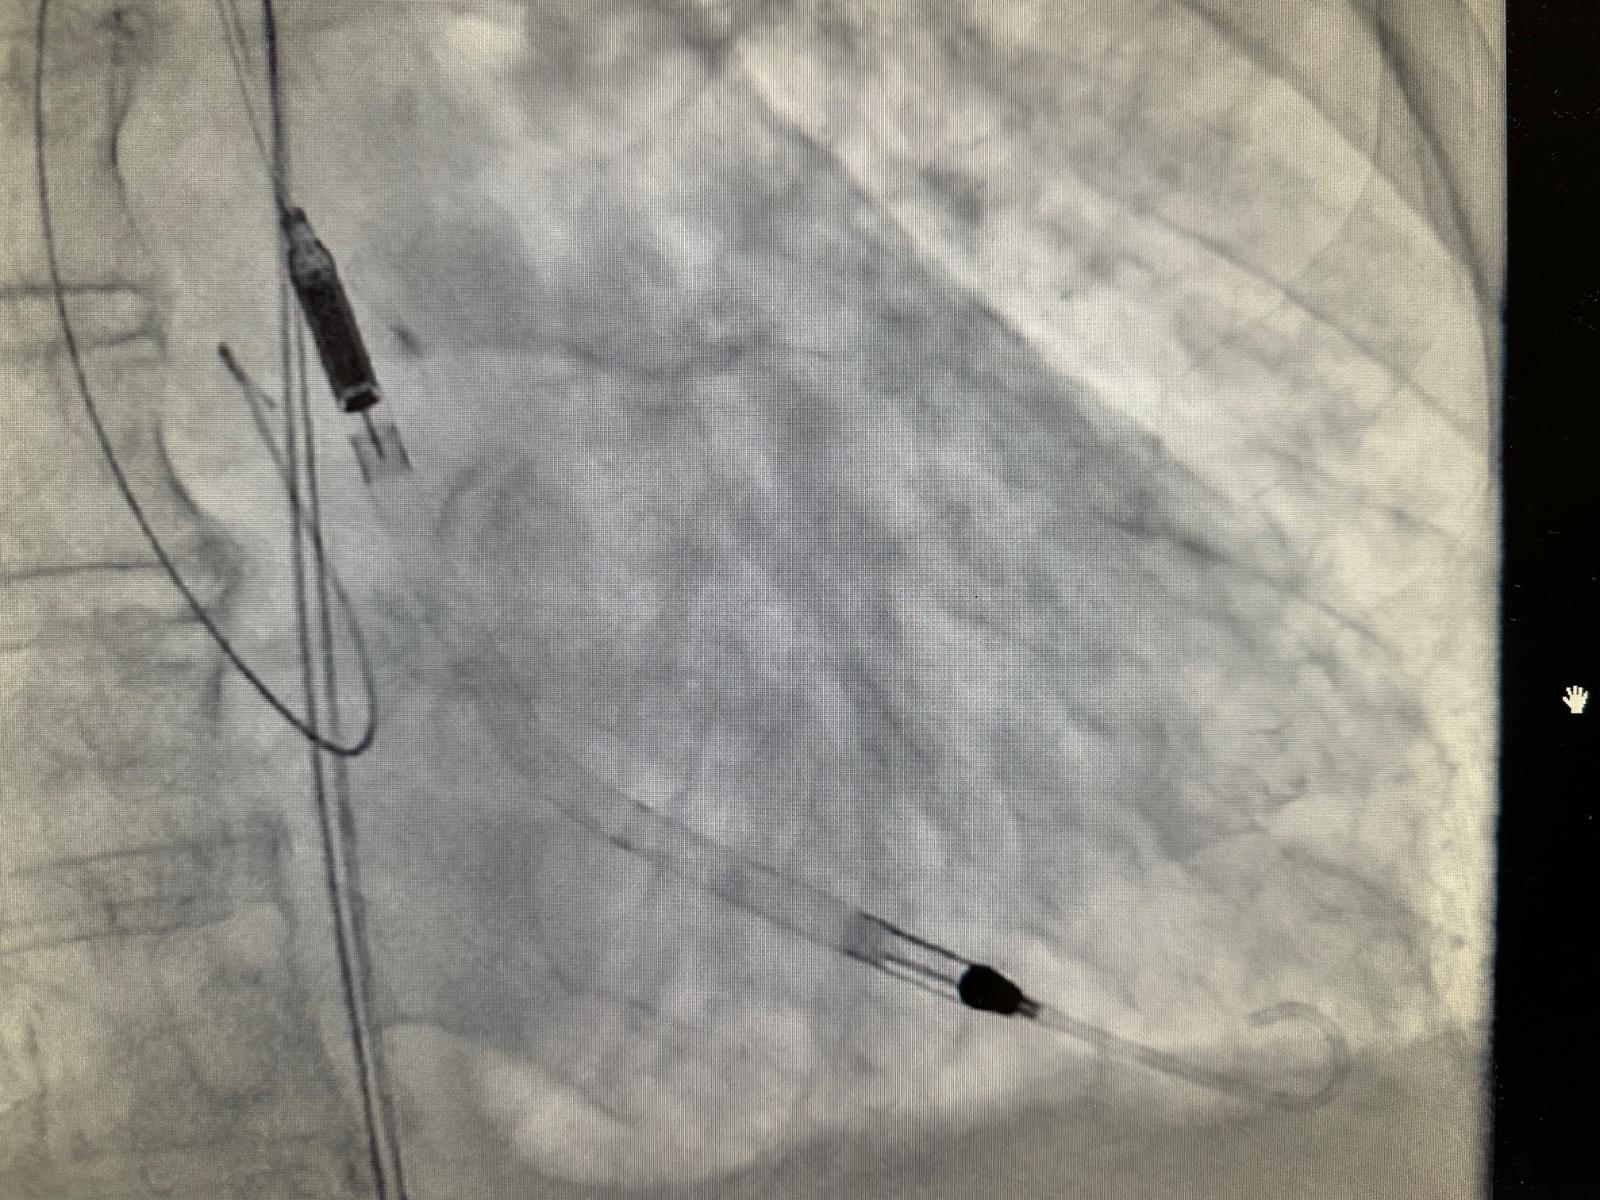

“Impella CP koristi tehnologiju perkutane srčane pumpe koja se kroz femoralnu arteriju uvodi u lijevu srčanu klijetku i pruža potporu radu srca kod visokorizičnih zahvata i srčanog zatajenja. Uređaj osigurava protok krvi do 4.3 litre u minuti, čime značajno smanjuje opterećenje srca i pomaže pri održavanju cirkulacije.

Ova tehnologija predstavlja vrhunac suvremene medicinske skrbi za pacijente u kardiogenom šoku ili pri izvođenju visokorizičnih PCI zahvata. Impella sustav postaje standard u svjetskoj i hrvatskoj praksi te je uvršten u Nacionalni kardiološki tender i time postaje sve važniji alat u borbi za život pacijenata s teškim srčanim stanjima”, izjavio je voditelj Odjela intervencijske kardiologije Mihajlo Kovačić, dr.med. spec.interne medicine, subspec. kardiologije.